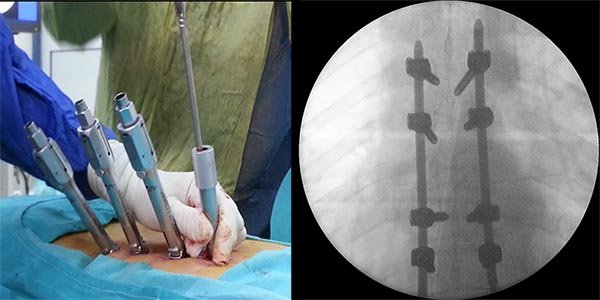

Figura 5:

Caso 8. Se realizó una estabilización percutánea T6-T10. El paciente retornó a UTI, para estabilizar su cuadro respiratorio y hemodinámico.